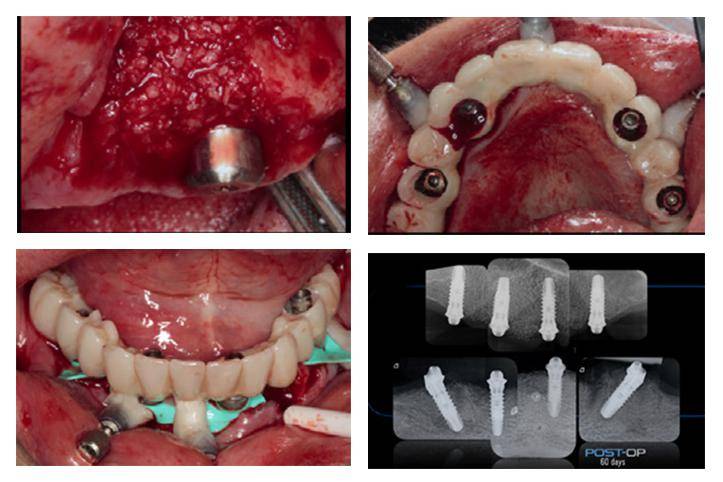

病例分享 | 下颌无牙颌即刻固定修复一例_百齿泰_种植牙_百齿泰(厦门)

图片尺寸860x577